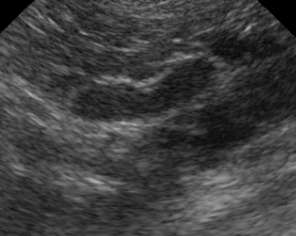

Imagem ultrassonográfica da glândula adrenal esquerda normal de um cão.

Na imagem ultrassonográfica, as adrenais têm a cortical menos ecogênica e a medula mais ecogênica. A adrenal esquerda tem uma constrição central e pólos mais arredondados, o que faz com que pareça um “amendoim” ou “haltere de academia”. Já a direita tem forma de “vírgula” ou “bumerangue”, com extremidades assimétricas.